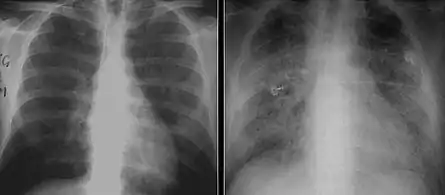

The diagnosis can be confirmed by the characteristic appearance of the chest X-ray and an arterial oxygen level (PaO2) that is strikingly lower than would be expected from symptoms. Gallium 67 scans are also useful in the diagnosis. They are abnormal in about 90% of cases and are often positive before the chest X-ray becomes abnormal. Chest X-ray typically shows widespread pulmonary infiltrates. CT scan may show pulmonary cysts (not to be confused with the cyst-forms of the pathogen).

Chest X-ray of increased opacification (whiteness) in the lower lungs.

These chest radiographs are of two patients. Both show ground glass opacities. The left X-ray shows a much more subtle ground-glass appearance while the right X-ray shows a much more gross ground-glass appearance mimicking pulmonary edema.[7]

X-ray of a cyst in pneumocystis pneumonia[7]